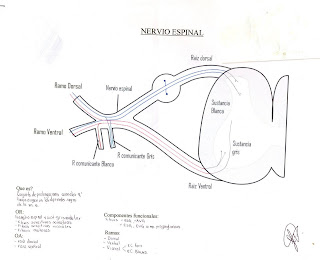

8.- El nervio espinal está compuesto por una raíz dorsal sensitiva y una raíz ventral motora. Por esto sabemos que la cabeza de la neurona que llegó al asta dorsal está en el ganglio espinal y que del asta ventral salen motoneuronas que van a inervar a la periferia.

9.- El nervio espinal al salir se divide en una raíz ventral (forma plexos) y una raíz dorsal (inerva pared posterior del tórax).